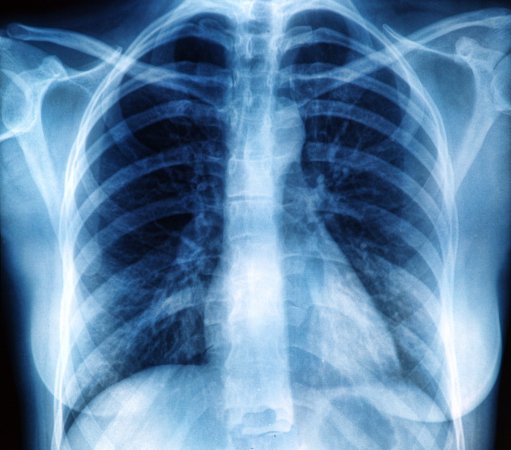

A doctor examines a chest x-ray.

Lung cancer accounts for about 1.8 million deaths per year globally. Deposit Photos